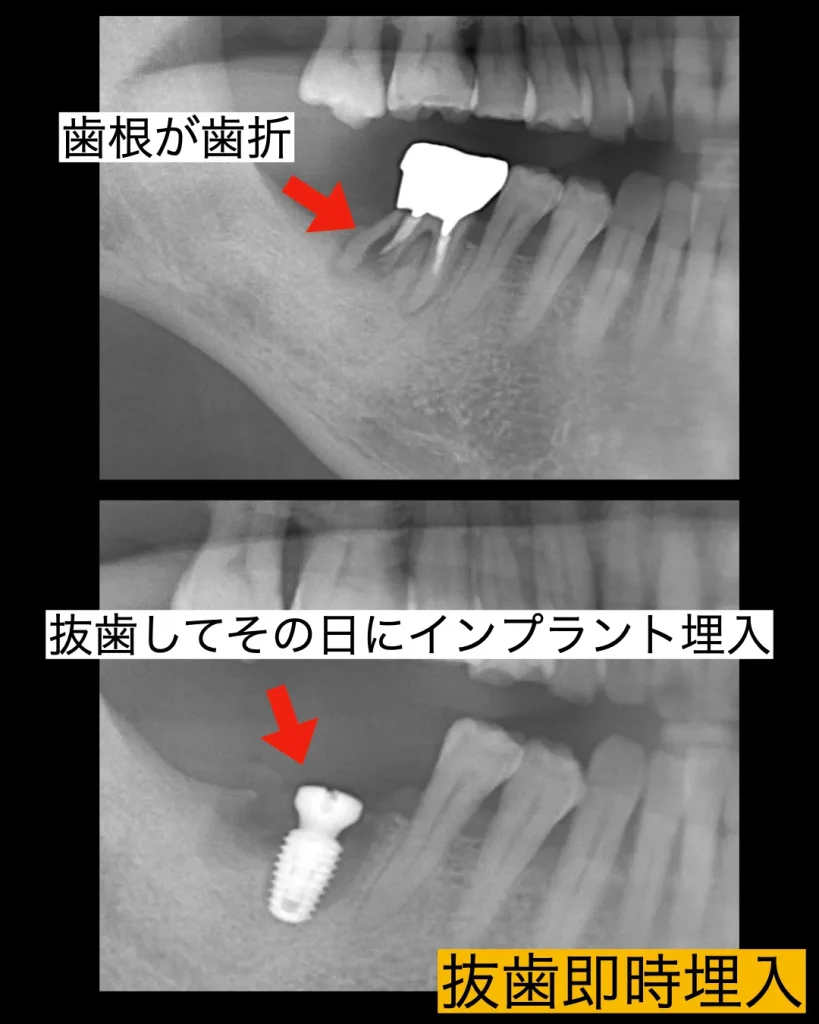

患者様は右下の奥歯が噛むと痛いという理由で当院を来院されました。レントゲンを撮影すると歯根が真っ二つに破折しており、膿もあり、周りの骨が大幅に溶けてしまっていました。診断の結果、幸いにもインプラントを支えることができる骨が一部分だけ残っていたので、抜歯してその日にインプラントを埋入する「抜歯即時インプラント」をご説明させていただきました。患者様は治療ができるだけ痛くなく、早く終わる抜歯即時インプラントの説明に納得され、インプラント治療を開始しました。

手術当日は、破折した歯を周りの歯茎を傷つけずに丁寧に、繊細に抜歯します。そして、インプラント窩をドリルで形成し、一部分残っているわずかな骨を利用しインプラントを固定しました。初期固定は強くとれ、インプラントを維持できたので、キャップ(歯茎を治すためのキャップ)をいれ、周りに少々の骨補填材とコラーゲンを挿入し治療を終了しました。